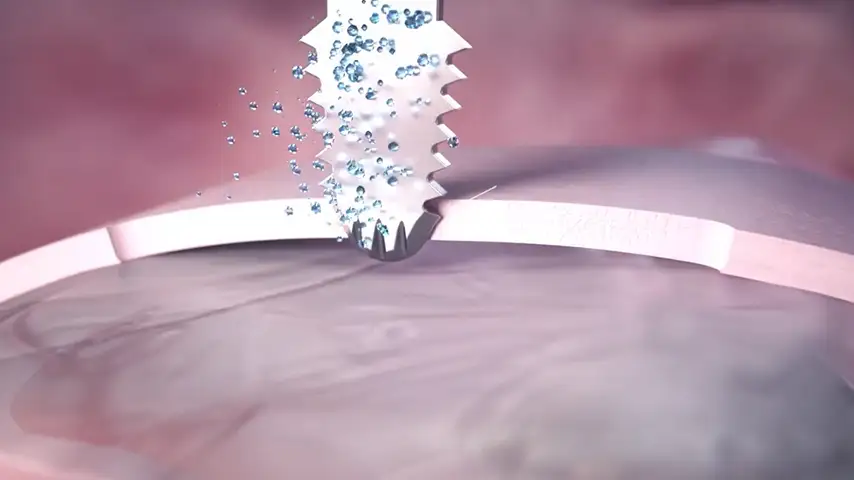

CAVITATION EFFECT

Maximum intra-operative visibility.

Blood-free surgical site.